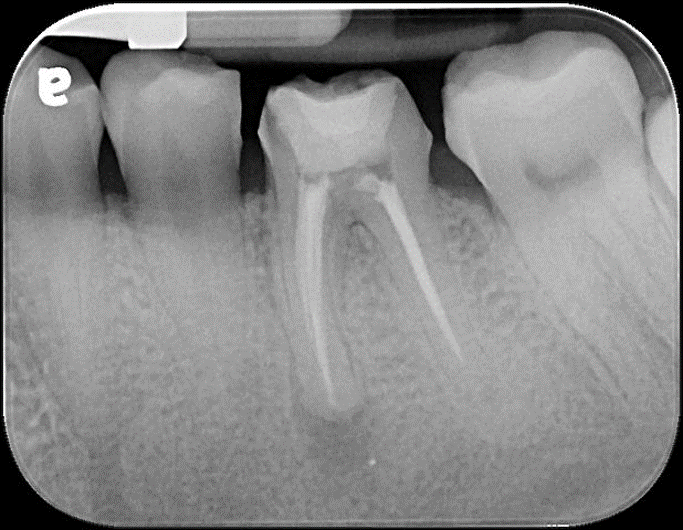

治療前,根管治療後